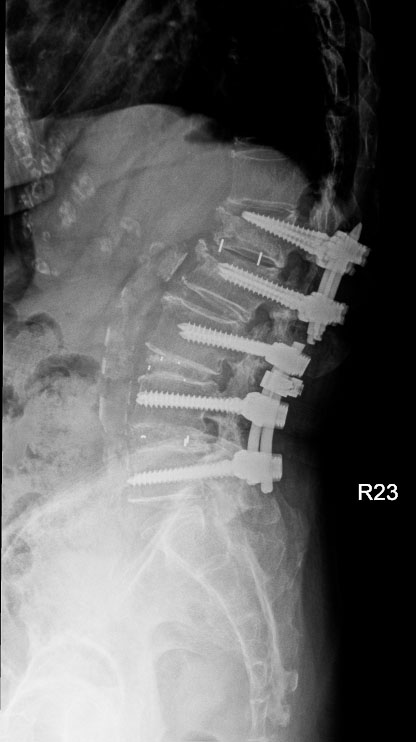

八十五歲的林女士在十多年前與七、八年前曾分別接受兩次腰椎手術,近來卻出現劇烈腰痛,翻身時疼痛指數高達八分,甚至難以入睡。影像檢查發現,她的腰椎第一與第二節出現嚴重狹窄,需要再次手術。

神經醫學中心團隊採用「截釘翻修技術」,處理高齡與多次手術史的複雜個案。「截釘翻修技術」的概念並非完全拆除舊有植入物,而是在原有固定系統仍可利用的情況下,截短或延伸固定桿,再重新連接新的固定結構,如此可以避免大範圍拆除植體與肌肉剝離。

林女士的手術過程順利,術後十天疼痛感即明顯緩解。兩個月後,她已能每天步行半小時,生活品質大幅改善。對她而言,最大的改變是終於能夠「一覺睡到天亮」。

神經醫學中心統計顯示,近兩年共有五十多名患者接受截釘翻修手術,平均出血量比傳統延長固定手術少約一百五十毫升。對於高齡或慢性病患者而言,出血量減少意味著感染與心血管負擔也隨之降低。

術前

術後

林女士術前與術後的影像檢查結果。